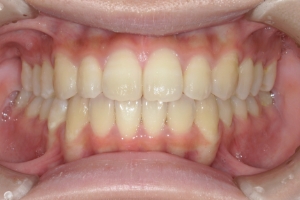

PROCESS

半年

AFTER

治療後

下の前歯が上あごの歯ぐきに当たるほど噛み合わせが深く、そのことが原因で上顎歯列の正中にすき間(正中離開)が生じていました。部分矯正ですき間を無理やり閉じても、噛み合わせが深いままでは治療後の再発リスクが高くなります。そのため全体矯正で奥歯の噛み合わせを整え、噛み合わせを浅くしつつ前歯を並べました。正中離開は戻りやすい傾向があるので、再発を防ぐため固定式リテーナーを推奨しています。